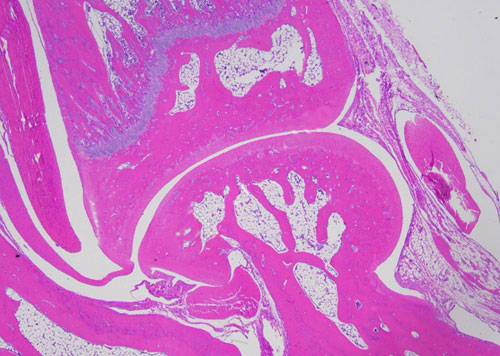

實驗結(jié)果展示:

正置顯微鏡型號:NIKON Eclipse ci;軟件:NIS_F_Ver43000_64bit_E;成像系統(tǒng):NIKON digital sight DS-FI2。可選擇 20×、40×、100×、200×和400×不同放大倍數(shù)。

(3)實驗結(jié)果:實驗結(jié)果:圖片×6(常規(guī)同視野下200×3、400×3)